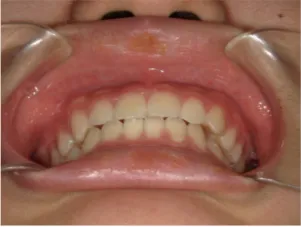

治療前①小1(7y2m):初診

*上顎前歯後方傾斜、上下唇の突出、口唇閉鎖不全傾向、コンケーブなし

| カウンセリング・診断結果 | 骨格的に下顎前方位で下顎骨も大きいタイプで、上の前歯が後ろに傾斜している受け口です。 顔立ちは上下唇が突出していて口唇閉鎖不全傾向がありますが、コンケーブにはなっていません(写真①)。 機能的に低位舌があり、今後受け口を助長する可能性があります。 受け口は、上顎骨の骨格的な前方向の成長を阻害し下顎が前へ強く成長していくため、骨格的な受け口が悪化し永久歯の咬合治療が難しくなり、症例によっては外科的な治療が必要になることがあるため早期に改善し骨格的な悪化を予防する説明をしました。 |